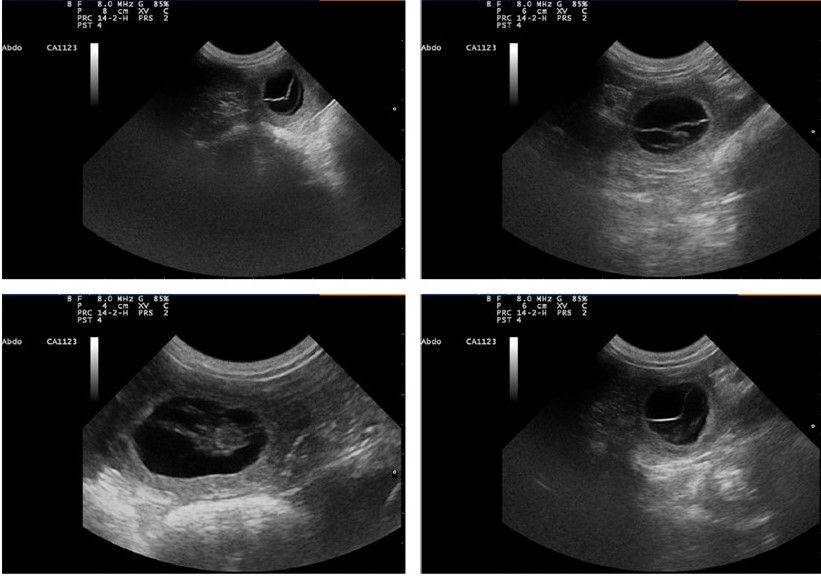

Diagnostique de Gestation

09/06/2021

Orka est bien gestante.

Mise bas prévue pour mi juillet.

13/03/2021

Noumaï est gestante

De très nombreuses réservations sont enregistrées.

Verdict par échographie dans trois semaines